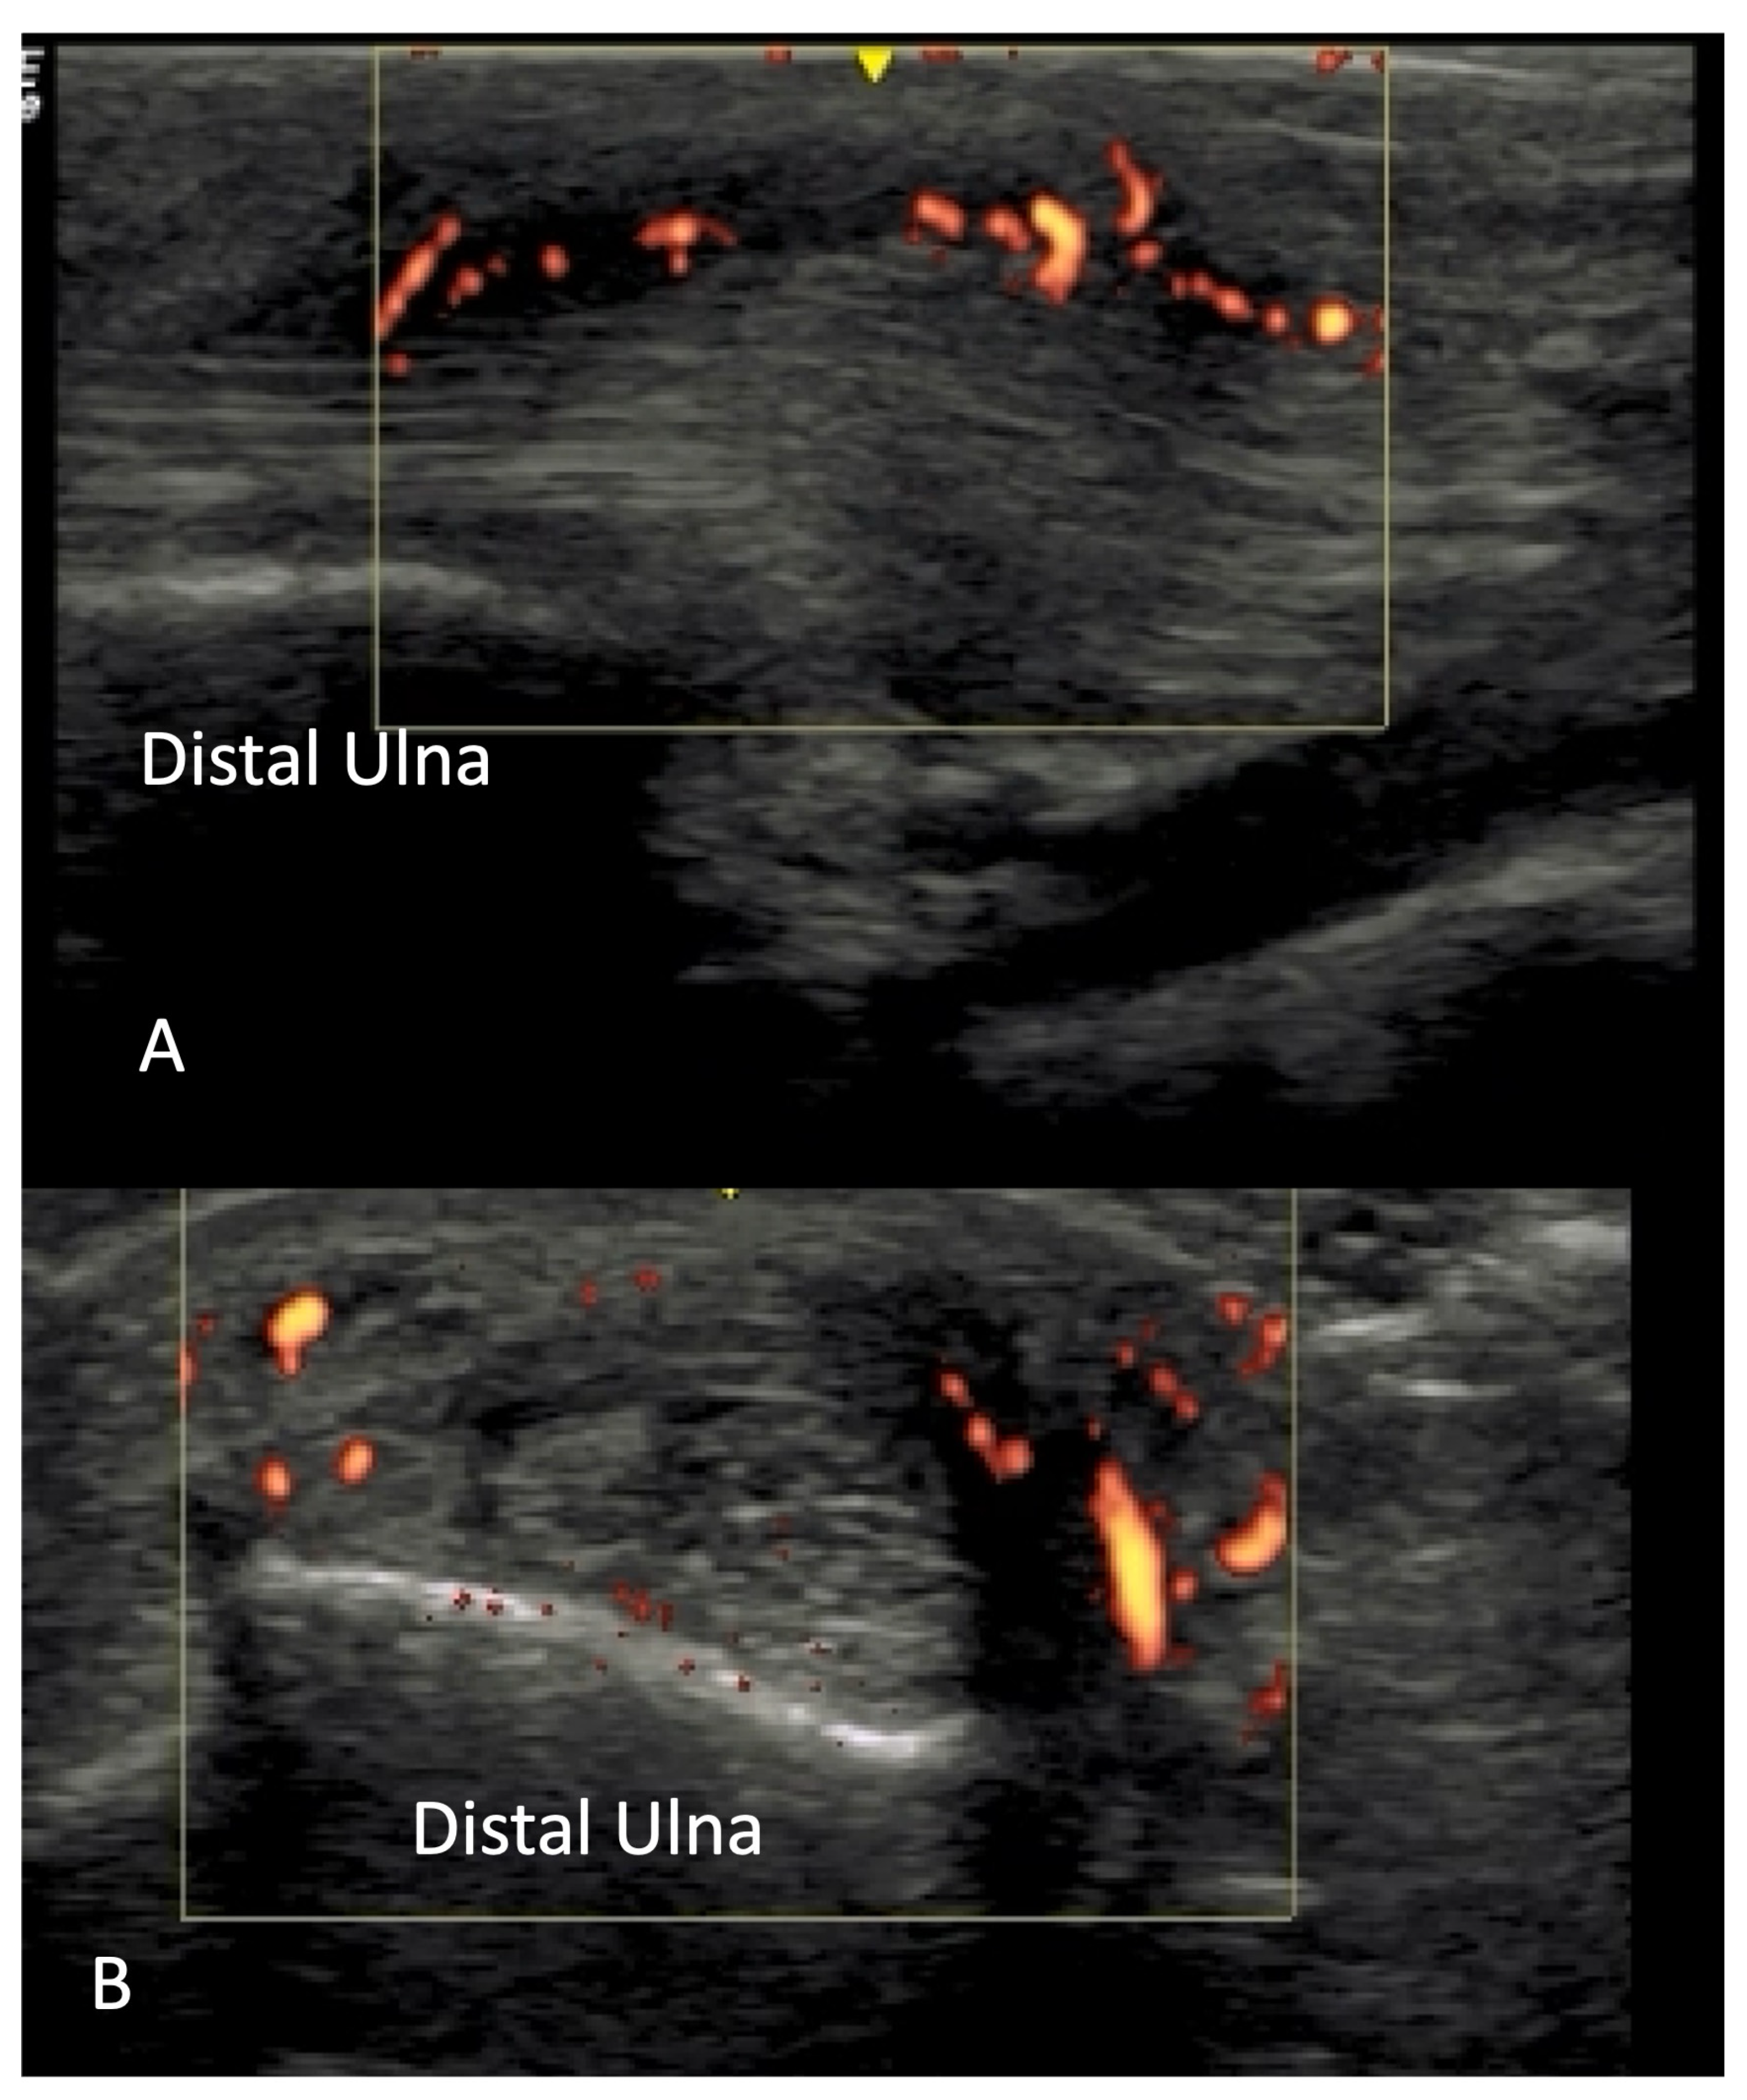

2.4. Vascular Pathology

2.5. Skin Thickening